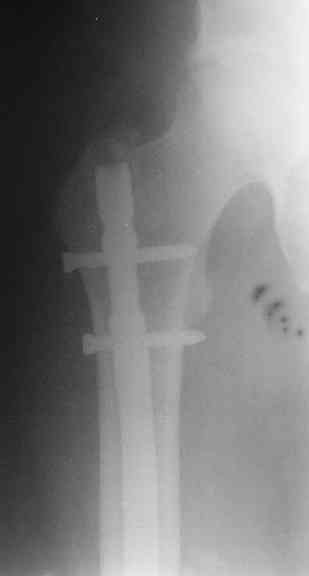

> денамизация - февраль 2006. ( 3 и 4 снимки) на сегодняшний день (снимок 5) беспокоит боли в тбс...

Однозначно: удалить, рассверлить, перештифтовать более толстым гвоздем. ЭТОТ 9 мм будет? Возьмите 12-14.

Дистально обязательно два винта! Проксимально можно один динамический. Больной будет счастлив на следующий же день!

Учитывая точку введения - верхушка б\вертела - что бы исправить варус взял бы соответствующий гвоздь: длинную Гамму или PFN или Recon

Судя по уровню перелома, винты в шейку избыточны, подойдет и диафизарный гвоздь. Все, что нужно, это тиски и труба. Загнуть сразу ниже отверстий градусов на 8-10, и вся недолга. Последние годы у нас это рутинная практика. Предызогнутые еще с завода гвозди неудобны тем, что они уже правый-левый.

Согласен, что 3,5 см укорочение этим снимкам не соответствует, за счет перелома и деформации - 1,5 см от силы. То есть либо ошибка измерения, либо приводящая контрактура, либо укорочение за счет другого отдела.

Согласен, что закрытый реостеосинтез с рассверливанием и коррекцией оси - это то, что надо. Мы бы ввели в центральный отломок статических 2-3 винта, и один динамический винт в дистальном отломке.